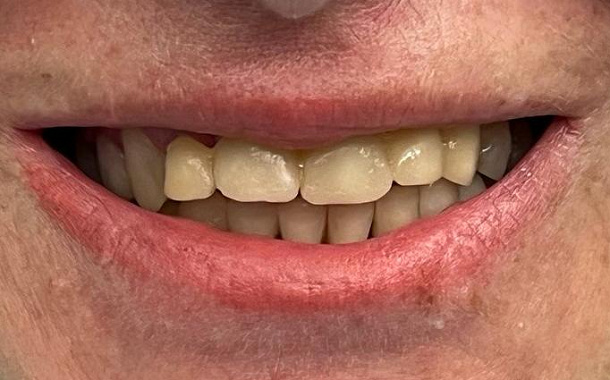

- Визуализация результатов: Пациенты могут увидеть предполагаемый результат лечения еще до его начала, что помогает в принятии информированных решений.

- Максимально точные и эстетичные ортопедические конструкции